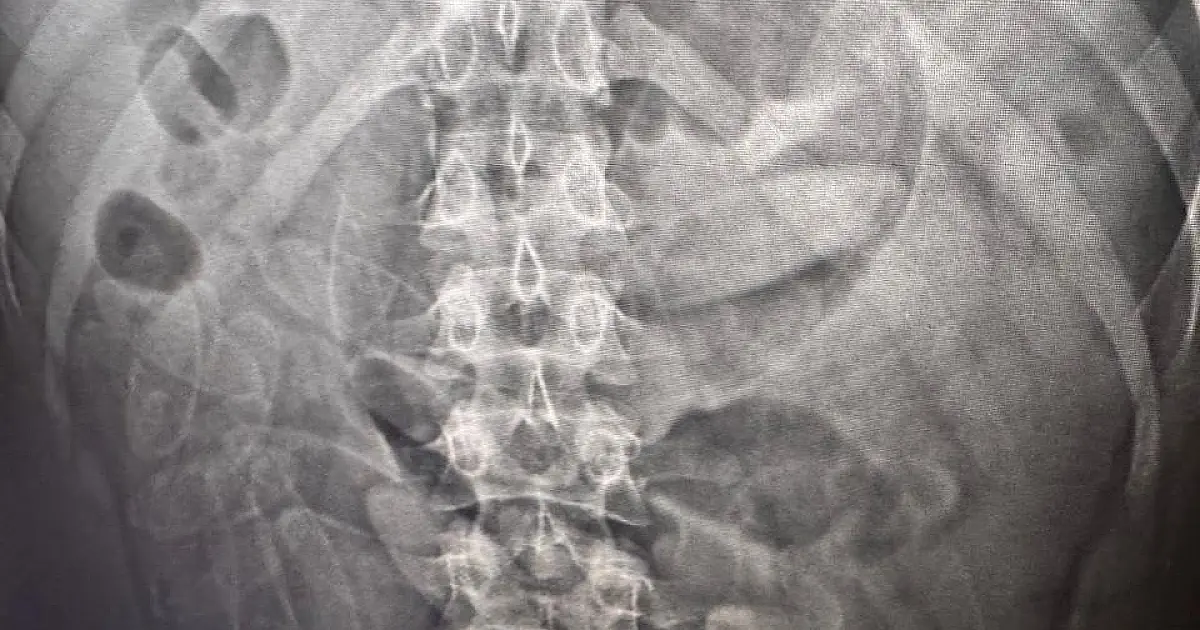

Seis bolivianos são presos traficando cápsulas de cocaína no corpo Grupo foi encaminhado à Santa Casa de Corumbá para expulsão das cápsulas de cocaína ingeridas. (Foto: Divulgação/RFB)

Durante a abordagem, no Posto Esdras, na fronteira com a Bolívia, foram identificados cinco indivíduos, de naturalidade boliviana, que haviam engolido cápsulas de substância análoga a cocaína. Todos foram levados a Santa Casa de Corumbá, sob custódia da PM e da RFB, para acompanhamento médico até que haja a expulsão de todas as cápsulas ingeridas e posterior encaminhamento à Polícia Federal.